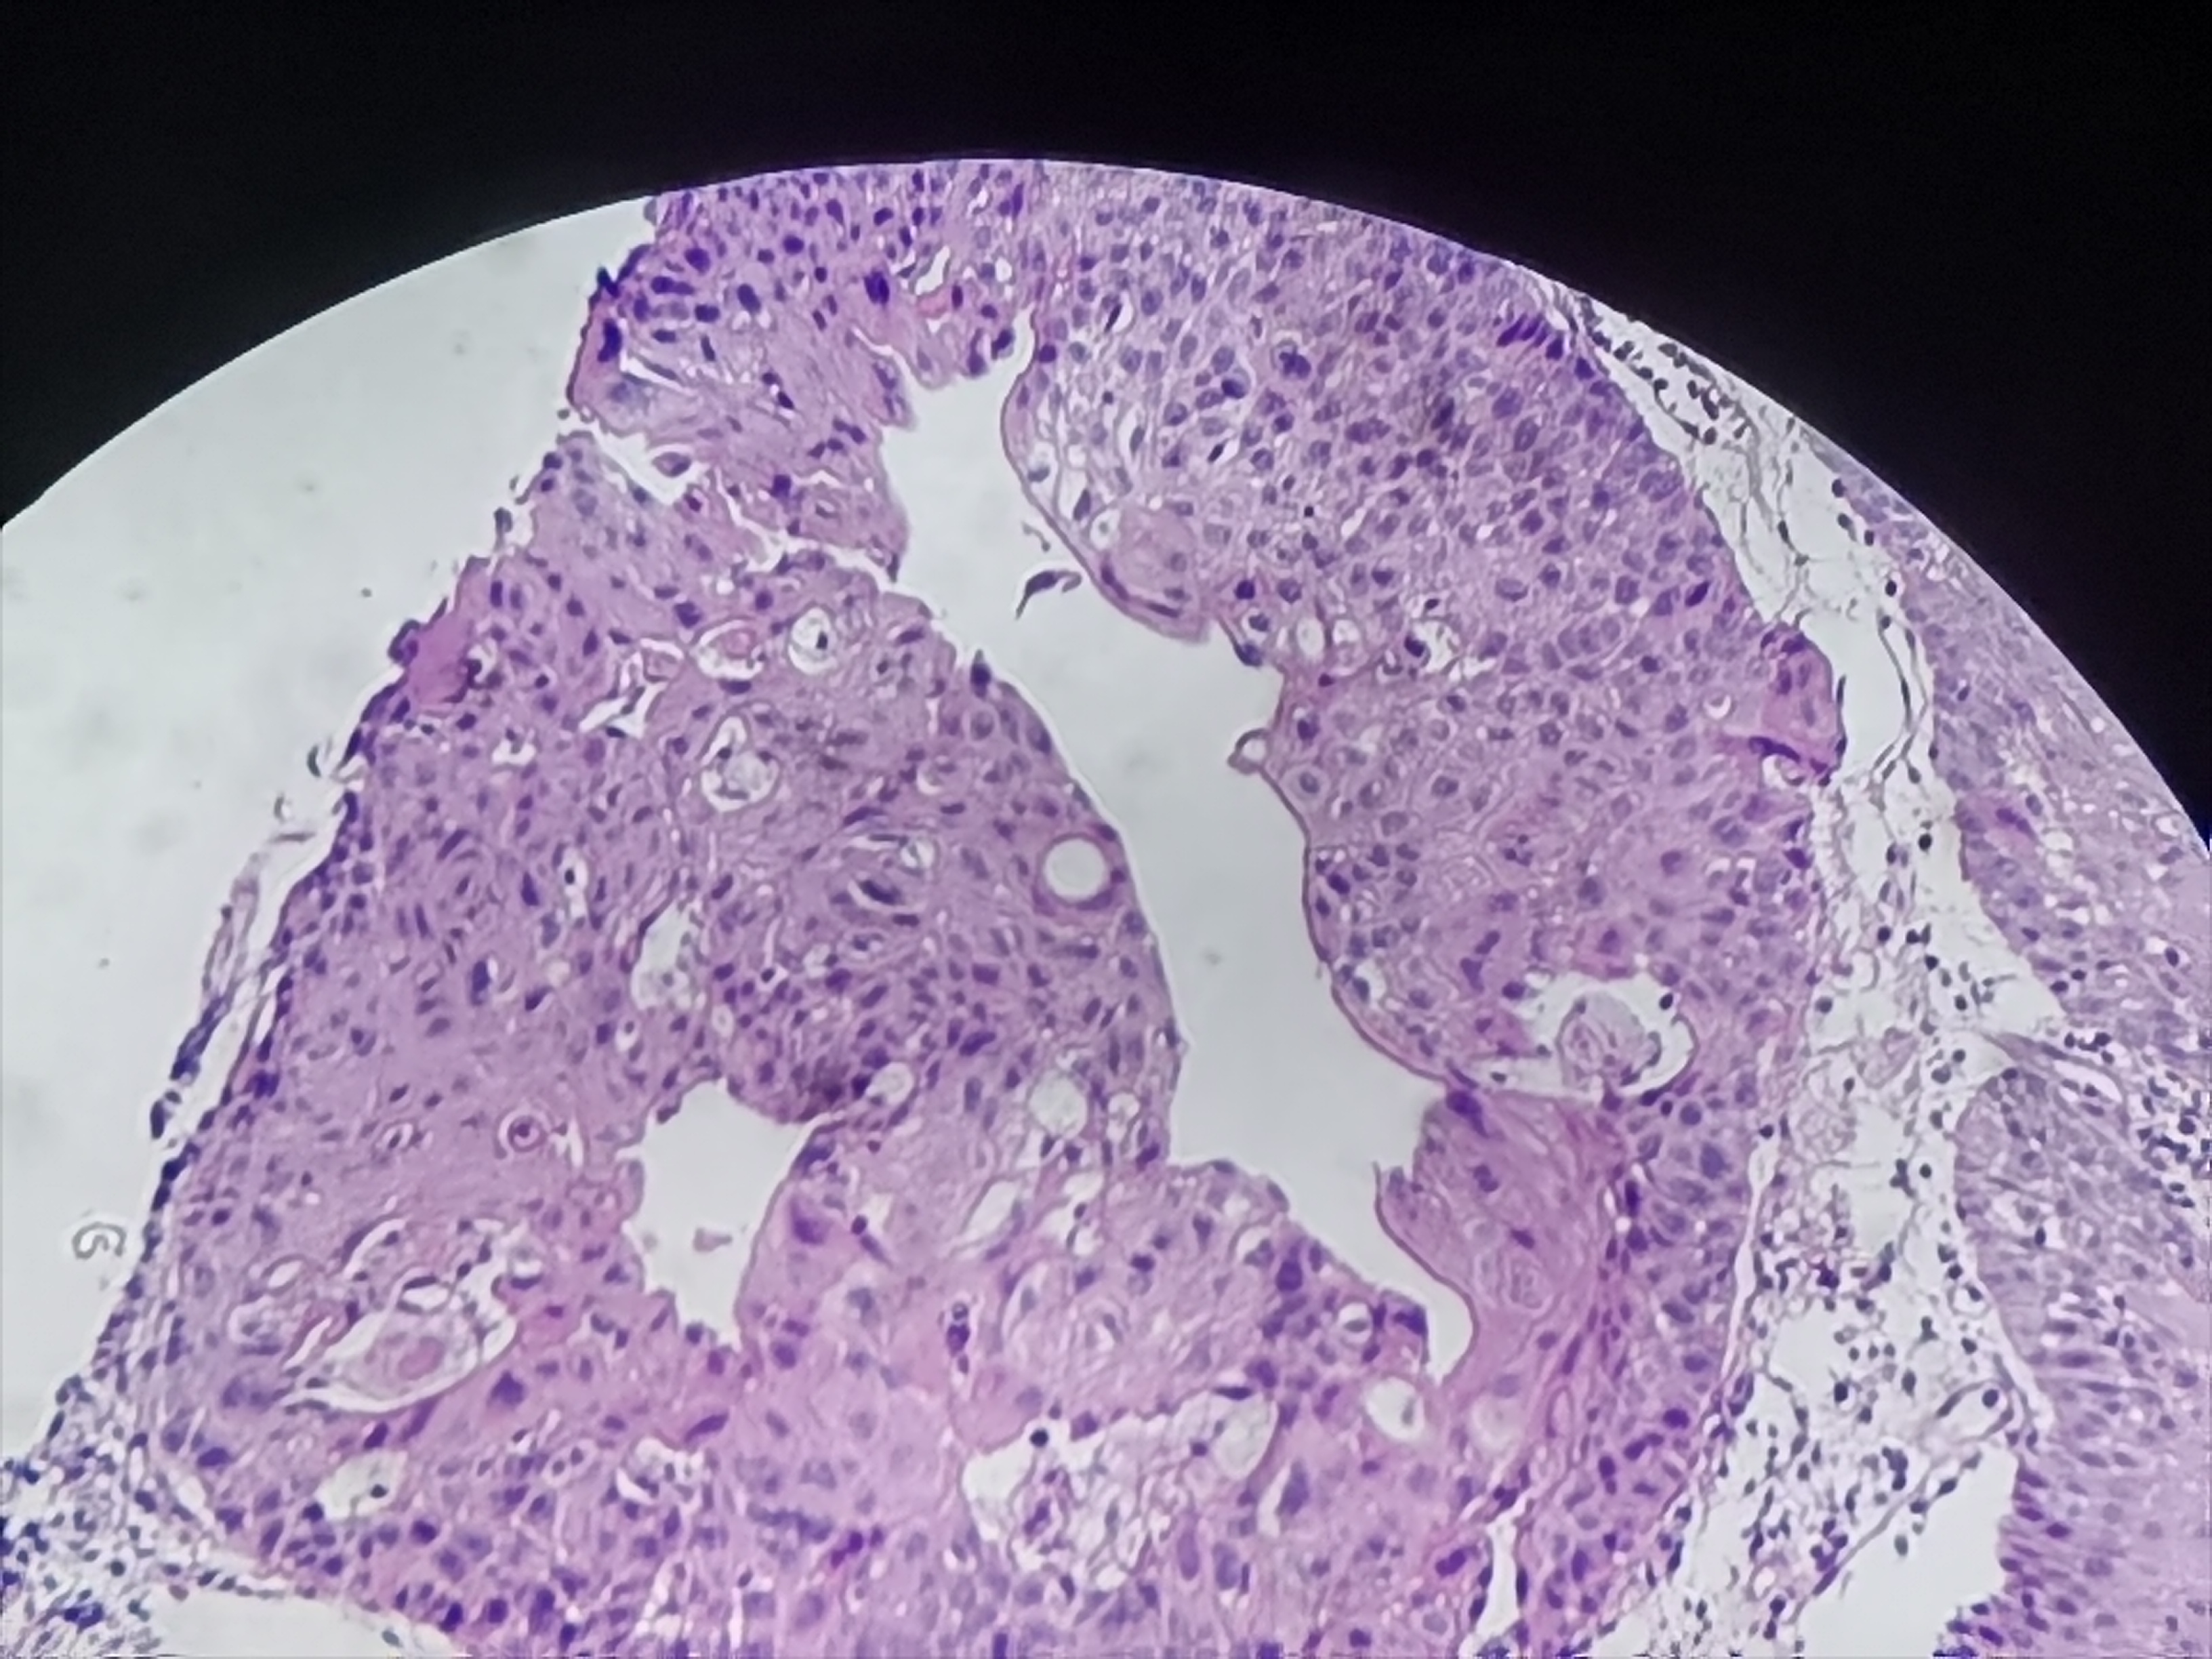

食管活检

性别

男

年龄

61岁

临床诊断

食管癌

一般病史

食管距门齿20cm处可见不规则病灶,质脆,易出血,管腔狭窄,镜子不能通过

标本名称

食管粘膜活检

大体所见

灰白色组织3块

考虑符合:鳞癌